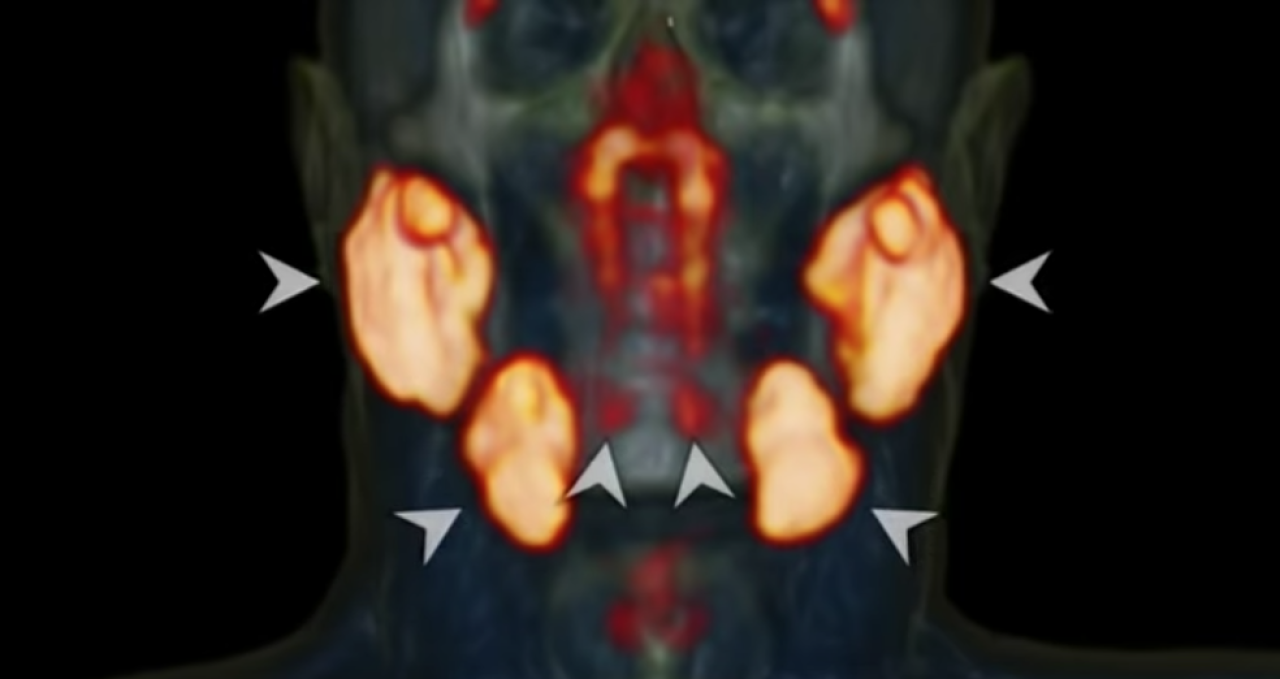

Hollanda Kanser Enstitüsündeki onkologlar, baş ve boyun kanserli hastalar üzerinde yaptıkları araştırmanın bir parçası olarak yeni bir tür tarama kullanıyorlardı. Prostat kanserinin vücutta yayılmasını izlemenin etkili bir yolu olduğu gösterilen prostata özgü zar antijen ligandları (PSMA PET/CT) taramaları ile pozitron emisyon tomografisi/bilgisayarlı tomografi kullandılar. Hastalara, taramadan önce parlak bir şekilde parlayarak hastadaki tümörleri vurgulayan radyoaktif glikoz enjekte edildi.

Ancak ekip, bu taramayı hastalar üzerinde kullanırken kafanın iki bölgesinin beklenmedik bir şekilde aydınlandığını fark etti. Hastaları taramaya devam ederken, aynı alanın aydınlandığını fark ettiler.  Taranan 100 kişinin hepsinin parlak noktaları olduğu ortaya çıktı. Bu bir anormallik değildi, potansiyel olarak tamamen yeni bir organdı.

Radyoterapi ve Onkoloji dergisinde açıklanan yeni keşif,  nazofarenksin arkasında konumlanmış bir dizi tükürük bezidir. Bunlar ağırlıklı olarak çoklu drenaj kanallarına sahip müköz bezlerdir.

Ekip bulgularını Amsterdam UMC'deki meslektaşlarıyla kadavra kullanarak doğruladı ve şimdi insanlığın en yeni organını bulundukları yere atıfta bulunarak "tüberyal bezler" olarak adlandırdı. Bezlerin, radyasyon alan hastalarda disfaji (yutma güçlüğü) dahil olmak üzere komplikasyonların bir nedeni olabileceğini ve bunları bilmenin onkologların potansiyel komplikasyonları önlemek için bu alandan kaçınmasına yardımcı olabileceğini öne sürüyorlar.